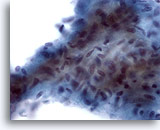

Figure 31

Breast FNA, Ductal carcinoma.

Under higher magnification the neoplastic cells show crowding and prominent nucleoli. The chromatin is abnormal though pale. 60x

Figure 31

Breast FNA, Ductal carcinoma.

Under higher magnification the neoplastic cells show crowding and prominent nucleoli. The chromatin is abnormal though pale.

60x